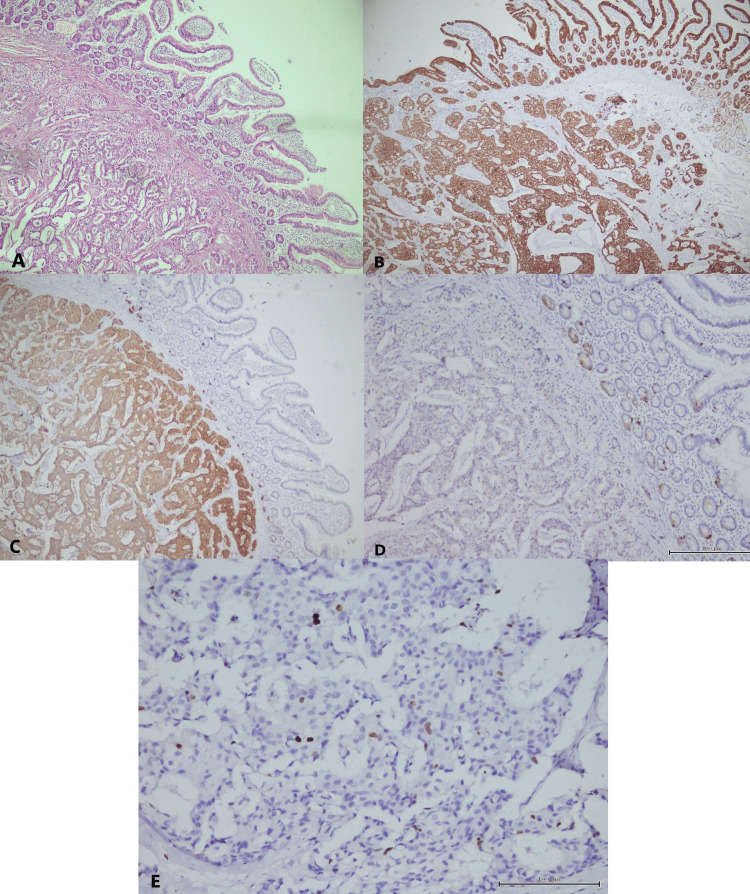

Microscopically, the periampullary region was lined by duodenal mucosa. The submucosa showed a neoplasm composed of cells arranged in nests, glands, trabeculae, and cords. It was infiltrating into the muscularis propria (Figure 3A). All resected margins were free. There were no lymphovascular or perineural invasions. The tumor was unifocal with a mitotic count of <2 mitoses/2 mm2. Five lymph nodes were dissected, of which one showed metastasis. On immunohistochemistry studies, the tumor cells were positive for pan-cytokeratin (Figure 3B), strongly and diffusely positive for synaptophysin (Figure 3C), and focally positive for chromogranin (Figure 3D). Only 2% of tumor cells were positive for Ki-67 (Figure 3E). Based on the histopathological and immunohistochemistry findings, the diagnosis of a well-differentiated NET, G1 (low grade), was established. According to the American Joint Committee on Cancer eighth edition, it was pT2N1M0.

Our patient did not have jaundice. Yet, before embarking on surgery for cholelithiasis, due to strong suspicion of ampullary malignancy evidenced by the double-duct sign on MRCP, we performed a UGI endoscopy with biopsy and subsequent histopathology. As NENs have glandular components such as adenomas and adenocarcinomas, our forceps biopsy during UGI endoscopy may have failed to obtain the complete tissue architecture needed for histopathology. It created a diagnostic dilemma. However, after the Whipple procedure, as soon as we received the histopathology report establishing the diagnosis of a well-differentiated NET, we asked for immunohistochemistry from a well-reputed center for further clarification. All markers (pan-cytokeratin, synaptophysin, and chromogranin-A) were positive in our case, supporting the histopathology. Besides, the mitotic count of <2 mitoses/2 mm2 and the Ki-67% index of <3% jointly confirmed the G1 (low grade) nature of the lesion as per the new WHO classification (2019) [ref. 3].